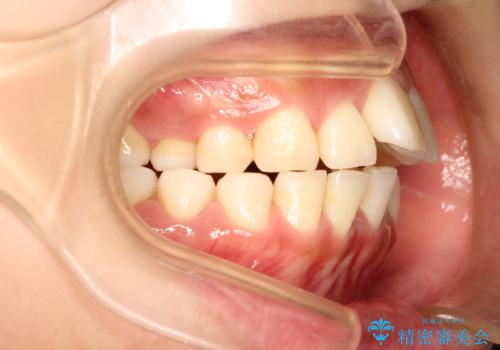

- 上の前歯が出てて、前歯で咬めないとのことで来院されました。

上顎の歯を1本抜歯して、前歯のガタガタと、前方に出ているのを改善する計画としました。

上下の前歯の距離が近くなり、前歯で咬みやすくなり、審美的にも改善できました。